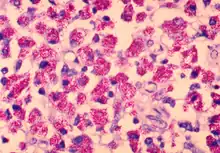

Mycobacterium avium is a species of the phylum Actinomycetota (Gram-positive bacteria with high guanine and cytosine content, one of the dominant phyla of all bacteria), belonging to the genus Mycobacterium.

Present mainly in cattle and humans with an immunocompromised disorder, e.g. AIDS, it is transmitted to man by drinking unpasteurized cow milk. Pigs are susceptible to M. avium avium , M. bovis, and M. tuberculosis, with M. avium being most common. Lesions are typically lymphoid, gastrointestinal, or rapidly progressive disseminated forms. Intradermal testing is the diagnostic test of choice. Isolation of purified protein derivatives is useful for M. bovis and M. tuberculosis. However, cross-reaction between M. avium avium, M. tuberculosis, or M. avium paratuberculosis is a disadvantage.